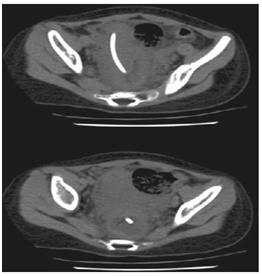

Abdominal X-ray and ultrasound (US) examinations confirmed the absence of peritonitis or pneumoperitoneum. However, CT abdomen revealed a hyper dense catheter projecting inside the descending colon. There was no free fluid in the peritoneal cavity (Figure 1). The patient was commenced on intravenous antibiotics and subsequently, the ventricular catheter was retrieved via an incision over the scalp. By pulling the protruding end through the anus, the distal catheter was then removed. The patient was kept under close observation for any sign of peritonitis or perforation for 5 days. Afterwards, she started oral feeding gradually and was discharged on the 6th day. No further problems were noted during regular follow-ups at the outpatient clinic.

Figure 1 Coronal sections of abdominal computed tomography showing distal catheter penetrating into the rectum.